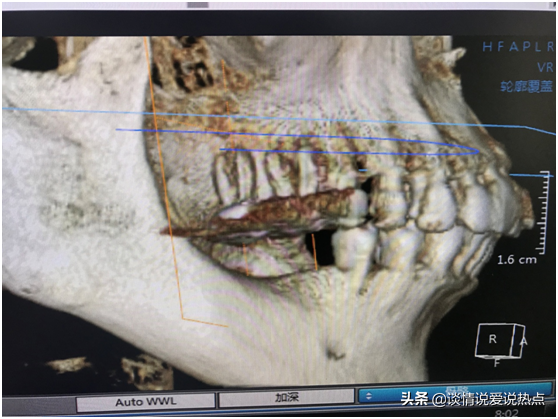

下圖是我現(xiàn)在右邊的牙齒,上頜做了根管調節(jié)戴冠,下頜缺失要種兩顆。醫(yī)生說我經(jīng)常用上頜咬東西,上頜有一顆戴冠的已經(jīng)伸長了,如果我再不管,三顆都會伸長。